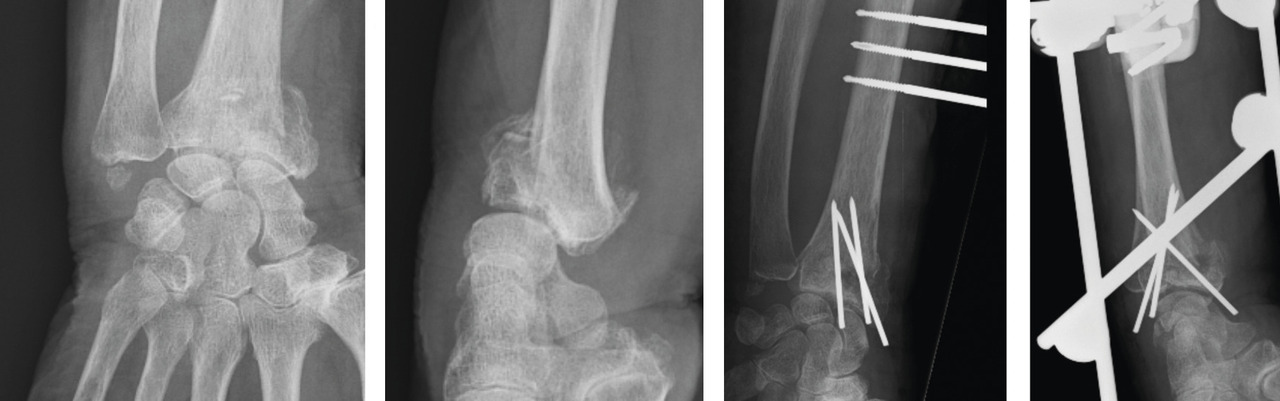

Les classifications lésionnelles utilisées à l’heure actuelle sont le fruit d’un processus de compréhension du traumatisme et de ses séquelles qui s’est échelonné sur plusieurs décennies. L’analyse de la fracture doit être focalisée sur les caractéristiques des 3 composantes anatomiques : métaphysaire, reliée au sens du déplacement fracturaire ; épiphysaire, reliée aux lésions articulaires ; et ulnaire, reliée aux lésions associées ostéoligamentaires.

Au niveau métaphysaire le déplacement peut être postérieur ou antérieur (fig. 6). En ce qui concerne le déplacement postérieur, il est important de se souvenir que la surface articulaire regarde vers l’avant. En d’autres termes, dès que cela n’est plus le cas, même si la surface articulaire n’est pas orientée vers l’arrière, il s’agit d’un déplacement postérieur. Classiquement, le déplacement postérieur est lié à un mécanisme dit en compression-­extension, c’est-à-dire une chute sur la main, le poignet étant en extension (fig. 7). Le déplacement est dit antérieur s’il y a une exagération de l’orientation antérieure de l’épiphyse radiale. Ce déplacement est classiquement lié à un mécanisme dit en compression-flexion, c’est-à-dire une chute sur la main, le poignet étant en flexion (fig. 7). La plupart du temps, ce déplacement postérieur ou antérieur s’accompagne également d’un déplacement externe, avec un tassement au niveau de la corticale latérale (fig. 8). Outre le déplacement antérieur, postérieur ou latéral, il est très important d’analyser au niveau du foyer de fracture métaphysaire l’importance de la comminution qui peut être uniquement postérieure, ou antérieure, ou circonférentielle, ce qui conditionne la stabilité de la fracture et oriente vers le type d’ostéosynthèse à réaliser.

Le traitement chirurgical, justifié en cas de déplacement non tolérable, repose sur 3 modalités pratiques distinctes : l’embrochage percutané, les plaques palmaires vissées, et le fixateur externe radiométacarpien, à ne jamais utiliser seul. Ces traitements remplissent le double rôle de réduction et de stabilisation de la fracture jusqu’à consolidation.

La mise en place des broches percutanées sont habituellement introduites dans le foyer de fracture, en arrière du radius, puis inclinées vers le bas pour réduire la bascule dorsale de la glène radiale et sont finalement fichées dans la corticale antérieure, épaisse, pour stabiliser la réduction obtenue. Il s’agit d’un embrochage « intrafocal » (dans le foyer de fracture). Une ou deux broches styloïdiennes dans le plan frontal complètent le montage. La bascule antérieure du fragment distal, la présence de refends articulaires, et la comminution métaphyso-épiphysaire sont indispensables à évaluer avant de proposer ce type de traitement et constituent des contre-indications relatives (fig. 12).

La mise en place de plaques palmaires nécessite un abord chirurgical antérieur et reste techniquement délicat, en particulier pour positionner la plaque en hauteur et pour la longueur des vis dont l’excès peut endommager les tendons extenseurs. L’indication phare reste les fractures métaphysaires à déplacement antérieur ou les comminutions métaphysaires étendues (fig. 13).

Enfin, le fixateur externe ne doit pas être utilisé seul car une traction excessive est un facteur de risque d’algo­neurodystrophie. Il doit être ajouté comme moyen de protection d’une ostéosynthèse par broche ou plaque précaire. Son rôle est de neutraliser les contraintes en compression sur l’extrémité inférieure du radius en cours de consolidation (fig. 14).